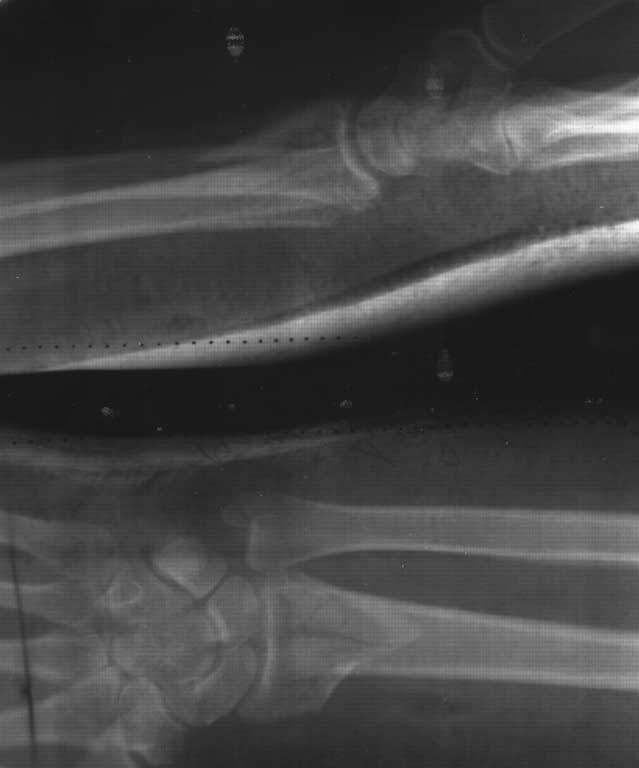

Имеется пациентка Ч. 42 лет. 20 мая 2012 года- перелом метаепифиза левой лучевой кости, со смещением отломков. После репозиции стояние отломков удовлетворительное. 10 июня 2012 - Р-контроль, имеется смещение отломков ( снимки прилагаются).

Вопрос: 1. Ваше мнение по поводу стояния отломков??? Шансы на сращение и удовлетворительность функции лучезапястного сустава???

2. Нужно ли оперативное лечение, если да, то предпочтительно какое ( остеосинтез пластиной или чрескостный остеосинтез)??? В анамнезе ведь было ЗНО слева...